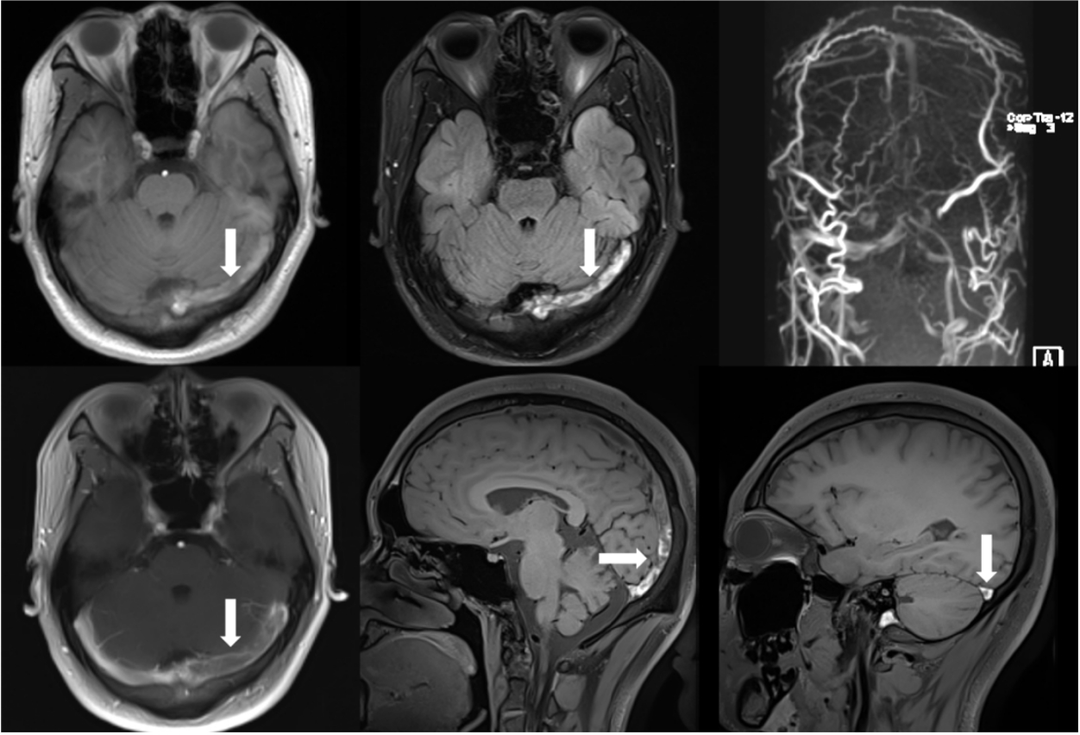

头MRI+MRV:左侧橫窦、乙状窦走形区异常信号,考虑为血栓。

复查静脉窦高分辨率MRI提示:左侧横窦、上矢状窦内血栓,左侧横窦内血栓量较前增加增加,复查腰穿压力290mmH2O,后转我科治疗。

病情分析:颅内静脉窦血栓好发于产褥期妇女,具有较高的致残率和致死率。该患者系青年男性,未发现明确病因,但是结合病史、D-二聚体增高、腰穿压力增高和典型的影像学检查,静脉窦血栓的诊断明确,给予抗凝及其他药物治疗病情仍持续恶化,考虑采取血管内治疗。高分辨磁共振显示目前的血栓仍较为新鲜且负荷量大,3D-MRV显示颅内皮层静脉开放而上矢状窦后部和左侧横窦闭塞,单纯全身抗凝治疗静脉窦内大量血栓难以接触到药物。

股动脉入路动脉造影显示上矢状窦后部和左侧横窦不显影,静脉期显影延迟,皮层静脉开放并明显增粗; 股静脉入路超选颅内静脉,微导丝和微导管引导ACE抽吸导管超选颅内静脉窦造影显示上矢状窦后部和左侧横窦内血栓影。